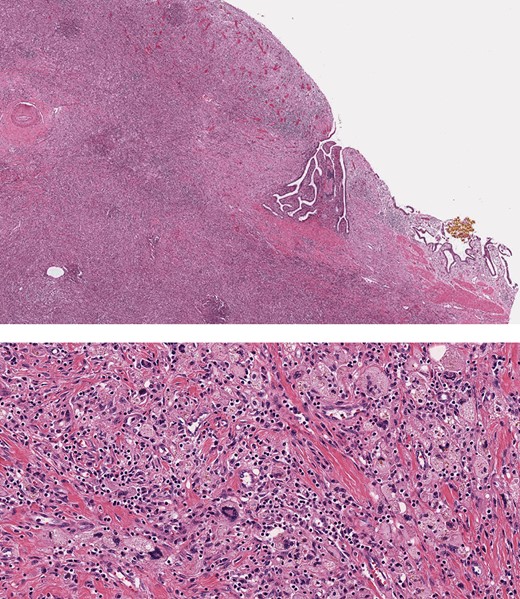

Intraoperatively, the surface of the liver was noted to be quite inflamed. There were dense pericholecystic adhesions, and the gallbladder was diffusely thickened. A hard mass with surrounding inflammatory and fibrotic changes was encountered in segment IV. After mobilizing the liver and controlling all hilar structures, in addition to Doppler confirmation of right hepatic artery flow, an extended left hepatectomy was performed. The right hepatic artery was carefully dissected off the mass, and the left liver including segments 5 and 8 as well as the caudate lobe was resected (Fig. 4). We were able to preserve the main bile duct. Pathology subsequently revealed XGC extending into the hepatic parenchyma (Fig. 5). After an uneventful post-operative course patient was discharged to extended care facility in stable condition 8 days after his surgery.

Histopathology, showing transmural inflammatory process in the gallbladder with mucosal ulceration (top) and the mass lesion composed of sheets of foamy histiocytes admixed with plasma cells, lymphocytes, collagen fibers and scattered giant cells (bottom).

XGC is a poorly understood and rare gallbladder disease that can mimic gallbladder cancer. There are several theories about pathophysiology, but the most widely cited one hypothesizes that increased intraluminal pressure in the gallbladder causes extravasation of bile into the gallbladder wall which is then taken up by activated histiocytes and fibroblasts causing a granulomatous reaction followed by cellular immune response and fibrosis [4, 5].